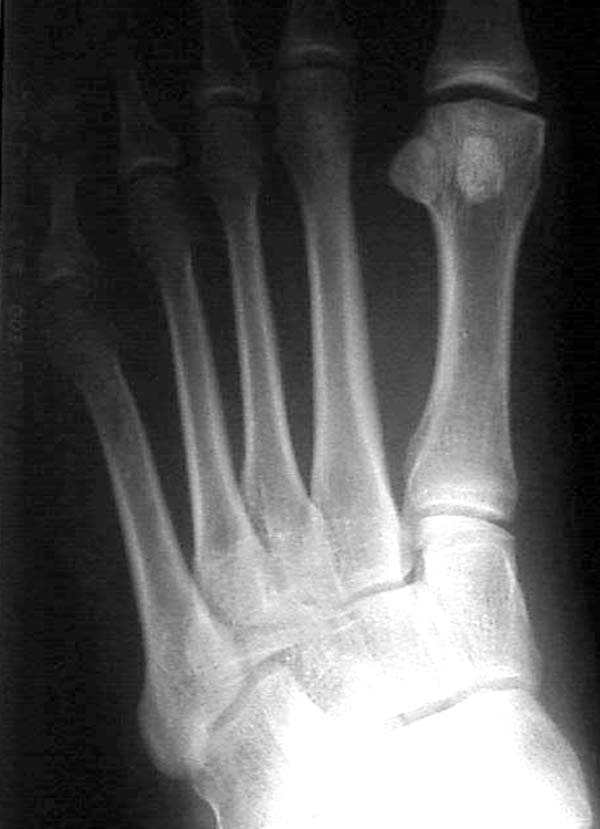

По снимкам нельзя исключить разрыв связки Лисфранка (связки между медиальной клиновидной костью и основанием второй плюсневой). Помогает в диагностике клиника (наличие изолированной гематомы на подошвенной поверхности стопы) и МРТ картина. Если связка повреждена - необходимо оперативное лечение.

по снимкам также нельзя исключить повреждение еще десятка -двух связок. Нормальные снимки.

По первому снимку, не видя больного, мог бы заподозрить перелом основания 3-й плюсневой кости. Поэтому избрал бы тактику консервативного лечения, как при переломе плюсневых костей без смещения!

Здесь КТ и сравнительные снимки стопы под нагрузкой.

Диагностировано повреждение медиальной и латеральной колонны.